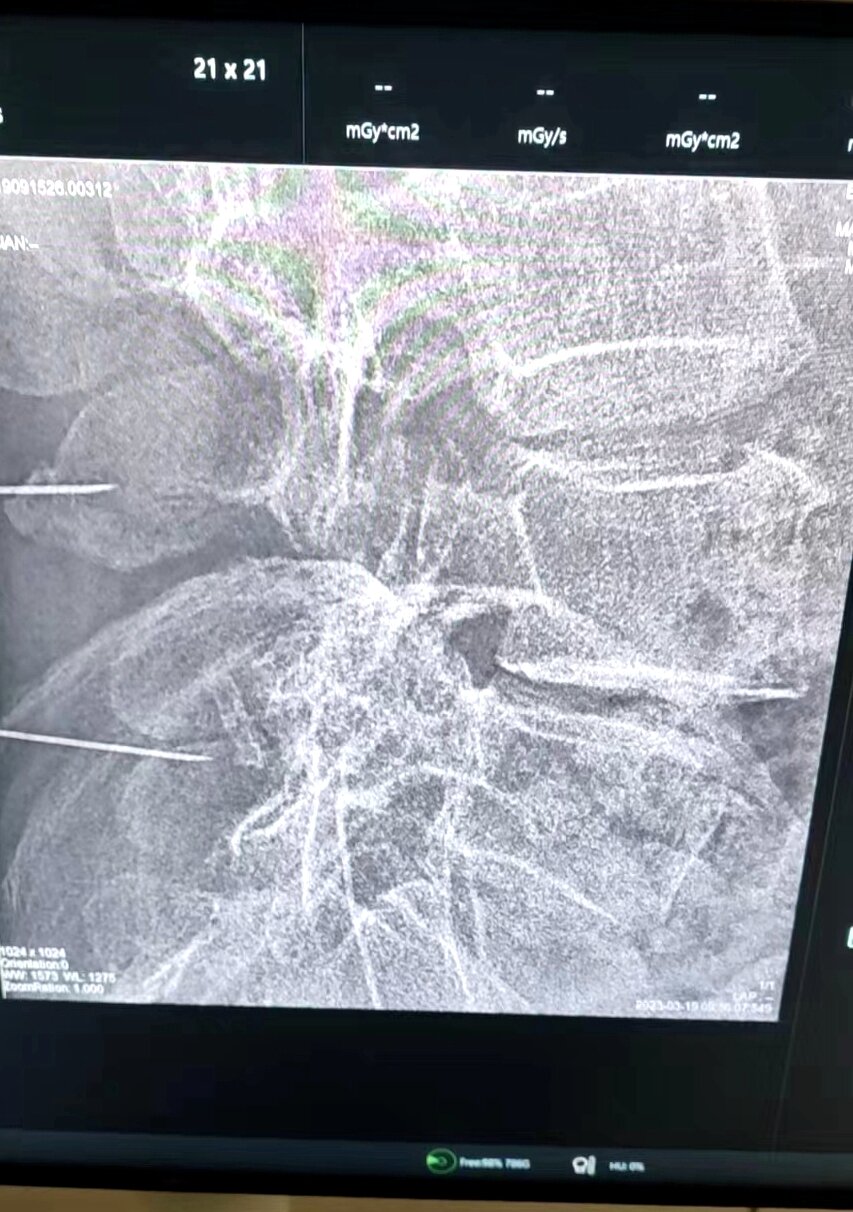

神經(jīng)外科副主任劉沛濤接診后,經(jīng)過詳細輔助檢查,診斷為L5神經(jīng)根病、腰椎滑脫、腰椎間盤突出癥,需手術治療。考慮到患者年齡大、體質差,傳統(tǒng)手術方式切口大,術后臥床時間長,顯微鏡下微創(chuàng)手術操作更精細,治療更精準,對患者機體損傷小,是目前治療脊柱脊髓疾病的首選方案,但微創(chuàng)手術對手術適應癥及手術技術的要求更高,因此科主任喬景尊組織科室團隊反復討論手術方案,進行充分術前評估后,劉沛濤及科室團隊在麻醉科通力合作下,采取顯微鏡下L5神經(jīng)根減壓+腰間盤切除+椎間植骨融合+釘棒內(nèi)固術,經(jīng)過2個多小時的謹慎、精細操作,順利完成了手術,患者安全返回病房。

神經(jīng)外科副主任劉沛濤介紹,神經(jīng)根病變的原因有椎間盤突出、椎管狹窄、椎體滑脫等,主要表現(xiàn)是腰痛、腿痛,傳統(tǒng)治療對于輕癥患者一般選擇藥物鎮(zhèn)痛、康復理療等方式,藥物及理療仍不能緩解的患者首選手術治療。傳統(tǒng)手術創(chuàng)傷大、出血量多、恢復慢,此次開展的顯微鏡下神經(jīng)根減壓術,利用人體腰椎自然解剖間隙,到達病變部位進行減壓,從而解除神經(jīng)根受壓,圓滿達到了治療目的。(通訊員:尹紅婭 李忠麗)